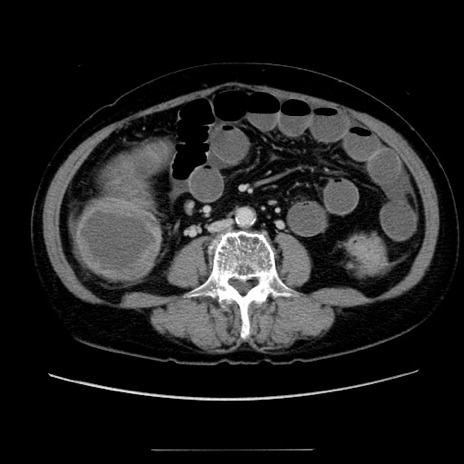

症例5(横断像)

【症例】70歳代女性

【主訴】お腹が張る

【現病歴】1週間くらい前から腹部膨満の自覚あり。昨日夜から増悪したため、本日救急外来受診。

【身体所見】意識清明、BT 36.5℃、BP 165/106mmHg、HR 80bpm、SpO2 98%、腹部:膨満、軟、自発痛・圧痛なし、触診にて不快感あり、腸蠕動音:減弱

【データ】WBC 12600、CRP 1.04